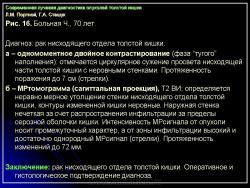

КТ толстой кишки значительно расширила возможности лучевой диагностики заболеваний полых органов желудочнокишечного тракта и в настоящее время стала более широко использоваться, в том числе и при опухолевых поражениях толстой кишки. КТ проводили после обязательного рентгенологического и эндоскопического исследований. На первом этапе серией последовательных срезов исследовали всю брюшную полость до области малого таза включительно. Для контрастирования просвета толстой кишки больному за 12 ч до исследования (после предварительного очищения кишечника) давали пить 5% раствор урографина – 500 мл дробно и 500 мл также дробно за 2 ч до исследования. Сложность и вариабельность формы и положения толстой кишки, изменчивость ее положения по отношению к продольной оси тела не позволяют получить стандартные томограммы, так как различные участки кишки попадают в срез продольно, поперечно или косо. Все это, вместе с различным содержимым в петлях кишки, затрудняет анализ состояния стенок кишки в зоне поражения. Если были сомнения в правильности полученной картины, то проводилось исследование зоны интереса с ретроградным введением воздуха в толстую кишку. Толщина кишечной стенки в норме зависит от степени растяжения кишки, но у здорового человека не превышает 5 мм.

Отображение опухоли толстой кишки на компьютерных томограммах зависит от локализации процесса и характера роста. При преимущественно диффузном внутристеночно растущем раке кишки, что выявлялось гораздо чаще, при КТ отмечалось утолщение стенки кишки с неравномерным, достаточно часто циркулярным сужением просвета соответствующего участка ее, ригидностью стенки (отсутствием изменения диаметра просвета и толщины стенки при дозированном введении воздуха) и неровными внутренними контурами (рис. 11). При экзофитном характере роста опухоли при КТ внутри просвета кишки определялось дополнительное мягкотканное образование с неровными бугристыми контурами, широко прилежащее к стенке кишки. Опухоли были различной структуры: однородной, неоднородной за счет включений кальция или участков распада с наличием в опухолевой ткани жидкости и газа. При появлении газа в околокишечной клетчатке чаще всего предполагалась перфорация ее стенки. Кроме оценки состояния стенок кишки, пораженной опухолью, оцениваются и изменения в окружающих тканях и органах при распространении ее за серозную оболочку. Степень местного распространения опухоли является одним из определяющих факторов прогноза и выбора дальнейшей тактики лечения. Оценку степени распространения опухоли проводили в соответствии с Международной классификацией по системе ТNM.

При КТ слои стенки кишки не визуализируются, в связи с чем разграничить стадии Т1 и Т2 не представляется возможным. Принципиально важно с точки зрения тактики дальнейшего лечения и прогноза заболевания диагностировать прорастание серозной оболочки кишки (Т3) и смежных органов (Т4). Одним из симптомов стадии Т3 является наличие в клетчатке, окружающей кишку, тяжистых или линейных структур, распространяющихся в виде лучей от стенки измененной кишки в жировую ткань или наличия узловой структуры вблизи наружного контура пораженной опухолью стенки кишки (рис. 12).